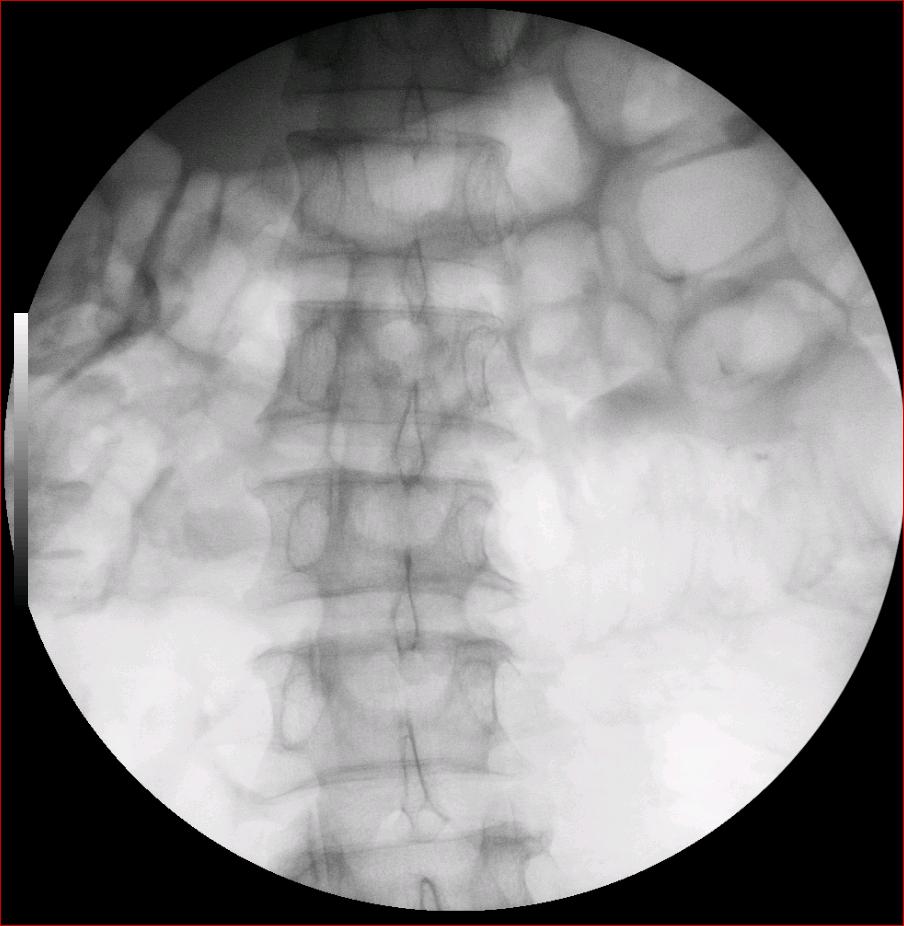

以下是引用luoxinjun在2008-2-18 15:54:00的发言:[br]右肾积水,右输尿管下端结石

以下是引用zhangxiangjun在2008-2-18 21:01:00的发言:[br]右输尿管盆段末端结石,继发其近端输尿管、右肾积水。

以下是引用hexue在2008-2-18 17:33:00的发言:[br]右输尿管下段结石并右肾及右输尿管积水扩张

以下是引用杀毒软件在2008-2-18 16:24:00的发言:[br]右输尿管下段结石,肾盂积水。